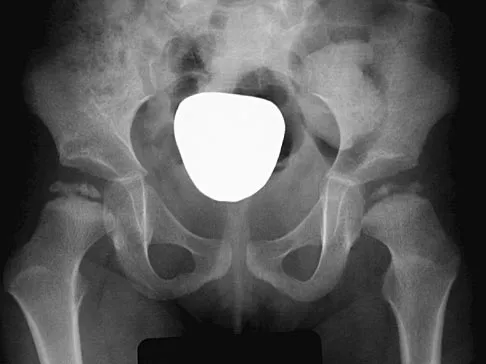

Question 6

A 3-year-old boy with severe cerebral palsy is unable to sit independently and does not crawl. Examination reveals a 40-degree hip flexion contracture by the Thomas test and 25 degrees of passive abduction. A radiograph of the pelvis shows subluxation of both hips, with a migration index of 30%. Management should consist of

Explanation